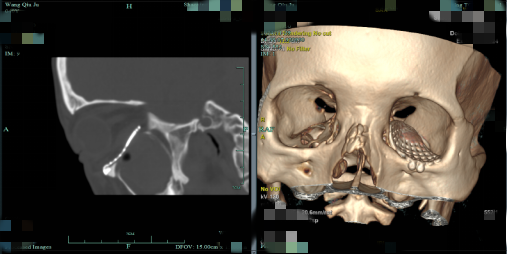

眼科诊疗组长傅杰副主任医师紧急前往会诊,王女士左眼眶周肿胀青紫,眶区凹陷约4mm,眼球上下转动受限,双眼复视明显,眼眶CT提示左眼眶下壁内壁骨折,下直肌嵌顿,上颌窦前壁骨折,鼻骨骨折。

术后,王女士的左眼不再凹陷,也能自由活动了,视物不再重影,疤痕也不明显!复查眼眶CT显示骨折复位良好,下直肌未见明显嵌顿。